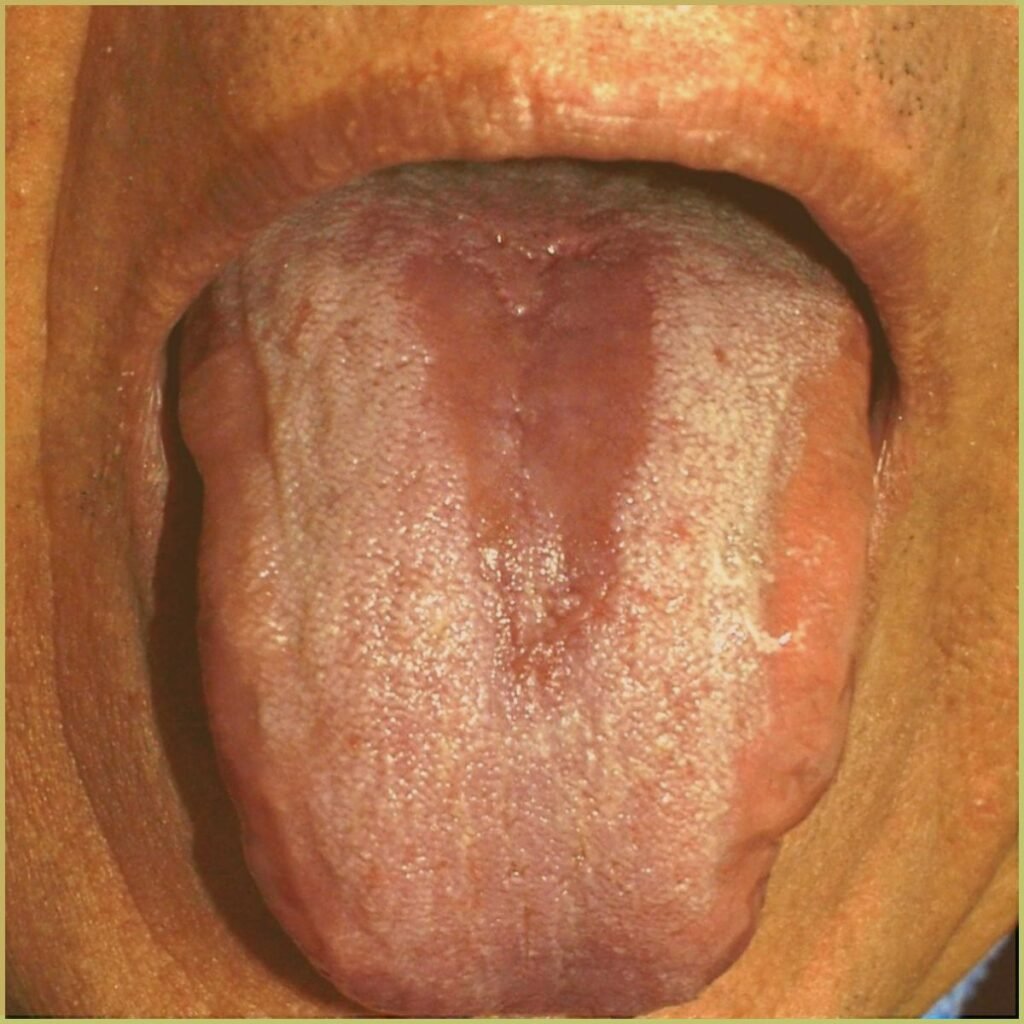

- Median rhomboid glossitis is a variation of hyperplastic candidiasis seen on midline dorsum of tongue anterior to circumvallate papillae.

Geographic tongue (migratory glossitis, erythema migrans) is a distinct condition appearing as a map-like pattern on the dorsum of the patient’s tongue. It is caused by the loss of dorsal papillae, but the reason for depapillation is not well understood. The common clinical presentation includes:

- Focal red depapillated areas bordered by yellowish margins.

- Areas of depapillation may migrate over time.

- Can be associated with fissured (scrotal) tongue.

- Primarily affects the dorsum (top) and lateral borders of the tongue, but can occasionally appear on other mucosal sites, such as the floor of the mouth and cheek mucosa.

- Some individuals may experience mild discomfort or a burning sensation, particularly when consuming spicy, acidic, or hot foods.

- Many cases are asymptomatic, with individuals only becoming aware of the condition during routine dental or medical examinations.

Diagnosis is usually based on the lesion history and clinical presentation alone. Your differential diagnosis should include:

- Lichen planus.

- Lupus erythematosus.

- Candidiasis.

- Psoriasis.

The condition is benign and self-limiting. Topical corticosteroids may be appropriate if the lesion is symptomatic.